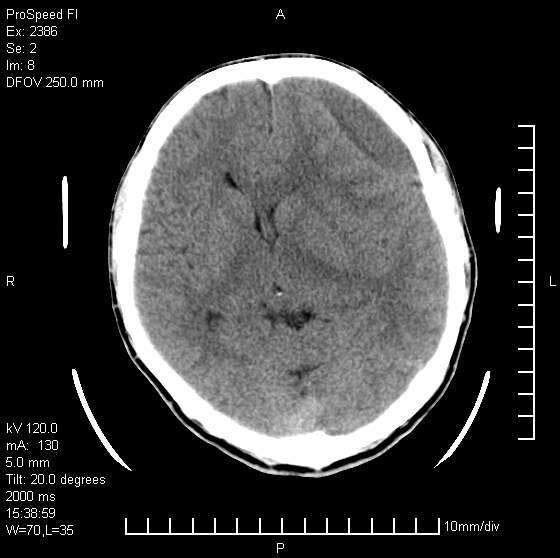

以下是引用天南地北在2007-9-19 18:43:00的发言:[br]典型慢性硬膜外血肿[br][br][本贴已被 天南地北 于 2007-9-19 18:44:11 修改过]

以下是引用曼一拍在2007-9-20 11:06:00的发言:[br]支持慢性硬膜下血肿.[br]慢性硬膜下积液:血肿有包膜,ct值稍高于脑脊液,增强可有染色。不典型者血肿可多呈梭形.是硬脑膜与蛛网膜之间的潜在腔隙内的血肿。[br]鉴别:[br]1\\硬膜外血肿:是颅脑外伤后脑膜或板障内血管破裂,血液在颅骨与硬膜之间积聚所致.通常是脑膜动脉破裂,也可因静脉窦破裂或颅骨的板障静脉出血,发生于外伤的着力部,常与颅骨骨折并存。脑膜动脉出血则急,若是板障静脉出血在则可有慢性。[br]2\\硬膜下积液:(硬膜下水瘤)[br]是由于蛛网膜破裂,脑脊液经蛛网膜破口进入硬膜下腔不能回流。或水肿阻塞而形成。[br]ct表现:颅骨内板下方新月形低密度区近似脑脊液密度;占位效应清,周围无脑水肿。[br]